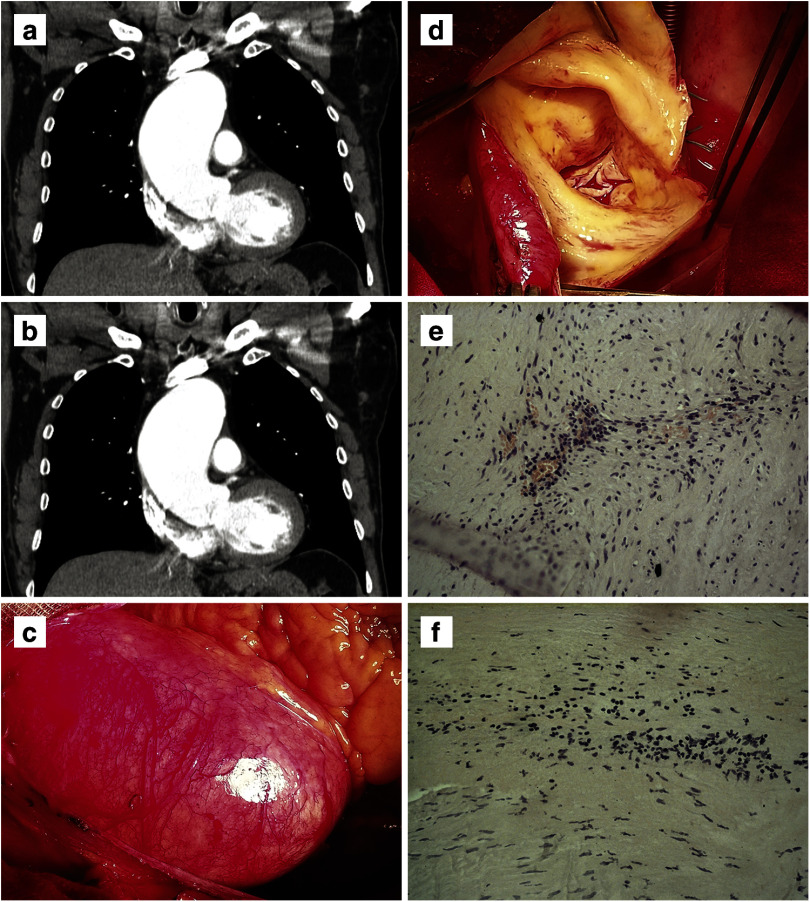

A syphilitic aortitis is a late cardiovascular lesion of tertiary syphilis that has become exceptionally rare in the antibiotic era but not eradicated completely. Syphilitic aortitis of ascending aorta complicates in ascending aortic aneurysm formation and aortic valve regurgitation, both requiring surgical treatment. After surgery, lifelong surveillance of the remainder of the aorta is recommended because of a priori supposed high incidence of delayed involvement of noninvolved aortic segments. A 3-year follow-up result of surgery of syphilitic ascending aortic aneurysm with aortic valve regurgitation in condition of active ongoing syphilitic aortitis and valvulitis is described with addressing the dimensions of remaining aortic segments. This case demonstrates that the dilatation of the remainder of the aorta does not occur during 3 years, at least when anti-syphilitic course of antibiotic is used just after operation without additional treatment during the follow-up period. A few reports on surgical treatment of syphilitic aneurysms of the ascending aorta are discussed.